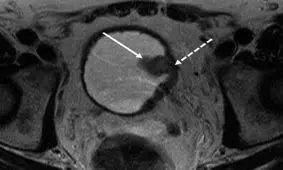

سرطان مثانه را با این علائم اولیه بشناسید.